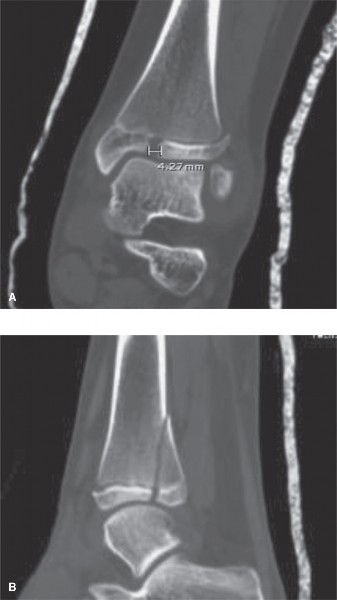

The correct answer is (D). In general, MRI is considered the “gold standard” for evaluation of soft tissue injuries, such as ligaments and tendons. dGEMRIC imaging (as its name implies) is used primarily to evaluate injury to the articular cartilage. CT scanning is generally considered the “gold standard” for evaluation of bony injury and alignment. Because your goal in evaluation post-reduction is assessment of the fracture alignment at the articular surface, a noncontrast CT scan is the best choice. Contrast enhancement in this setting would not add additional useful information. Post-reduction CT images are shown (Fig. 10–16A and B). Based on the images and measurement shown, you recommend (choose the best answer):

Figure 10–16 A–B

1. Continued immobilization, protected weightbearing with crutches, and serial radiographs to ensure maintenance of reduction

2. Continued immobilization, protected weightbearing with crutches, and serial three-dimensional imaging to ensure maintenance of reduction

3. Surgical reduction and internal fixation using a metaphyseal lag screw(s) construct

4. Surgical reduction and internal fixation using an all-epiphyseal lag screw(s) construct

5. Surgical reduction and internal fixation using a construct involving placement of lag screws in both the epiphyseal and metaphyseal fracture fragments

6. Surgical reduction and internal fixation using a physeal-spanning compression plate construct

Discussion

The correct answer is (E). In general, >2 mm of residual articular diastasis on radiographs is considered an indication for surgical intervention in an attempt to minimize abnormal joint contact forces and the resultant joint degeneration that occurs over time. This patient has >4 mm of residual articular gap measured on CT scan and is therefore a candidate for surgery. While surgical approaches to treatment of triplane fractures vary, one traditional approach is to reduce the articular surface (either open or percutaneously) and fix it in place using all-epiphyseal lag screws (with or without washers) placed perpendicular to the fracture line in an extraphyseal and extra-articular fashion. Depending on the size of the metaphyseal fragment, additional fixation with lag screws placed across the metaphyseal spike may optimize fracture fixation. This patient has a large metaphyseal fragment and would likely benefit from lag screw fixation in both the epiphyseal and metaphyseal fragments. Compression plating across a growth plate is not typically indicated.